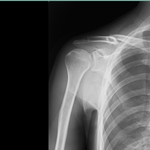

〇右鎖骨骨折

病院で手術の日程が決まっていましたが、保存的治療を希望されので当院で固定と経過観察をしました。(セカンドオピニオンとして整形外科医を紹介し同意)

骨折部位の転位がありますが正しい固定と注意深い経過経過観察、固定時期から積極的に周囲の血行を保つことにより経過良好で完治しました。

数多くの鎖骨骨折を診てきましたが、転位はひどくても正確な固定が維持できれば、かなりの成果があげられます。

今までに偽関節等で再度手術になった方はいらっしゃいません。

ちょうど暑い季節だったので、毎回固定を外し体をボディーソープで清拭しました。持参の下着に着替えてから再固定をしたのでストレスが少なかったと思います。